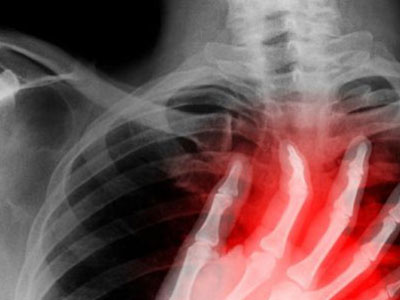

心絞痛可引起牙痛

老年人隨著年齡的增長,大腦及心髒神經纖維逐漸產生了退行性變化,對疼痛的敏感度降低,以致心絞痛的部位可以在胸骨內或心前區,也可放射到下颌骨、下牙齒,於是就產生了心源性牙痛。